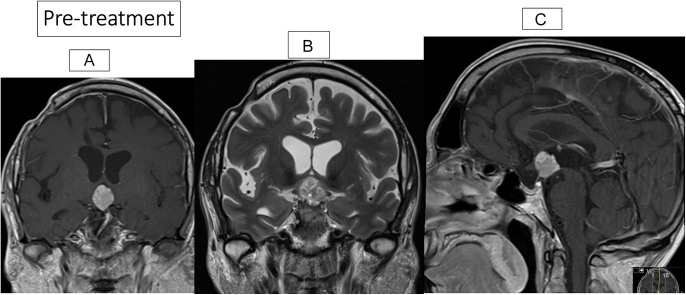

Summary: Craniopharyngiomas (CPs) are rare brain epithelial tumours arising in the suprasellar region, infiltrating adjacent areas causing visual loss, panhypopituitarism, cognitive deficits and morbid obesity. Papillary CPs (PCPs) harbour in 94% BRAF mutation cases. Two patients with PCP and BRAF V600E mutations but with different tumour status were treated with BRAF and MEK inhibitors. Case I was diagnosed with biopsy and treated for 16 months with BRAF and MEK inhibitors. After 3.5 months, there was a 50% reduction of the tumour volume, and after 13 months, the tumour volume decreased from 2220 to 90 mm3 (96%). Two months after stopping the drugs, he was treated with fractionated cranial irradiation (54 Gy). No recurrence of the PCP was recorded. Eight months after stopping the drugs, he was diagnosed with an adenocarcinoma of the oesophagus, which led to his death 12 months later. In case II, a woman had had four surgeries due to recurrences of a PCP, and a BRAF V600E mutation was confirmed. After a new recurrence measuring 14 × 12 × 18 mm, she was started on BRAF and MEK inhibitors. After 4 months of treatment, a significant decrease to 8 × 9 × 13 mm was recorded. The treatment continued for 31 months, and the MRI demonstrated a stable unchanged size including scar tissue, with a volume reduction from 633 to 483 mm3. During treatment, her visual acuity improved in her left eye from 0.05 to 0.3. After stopping the drugs, 'watchful waiting' with repeated MRI was decided. She is now off treatment for 25 months, without any recurrence on MRI.